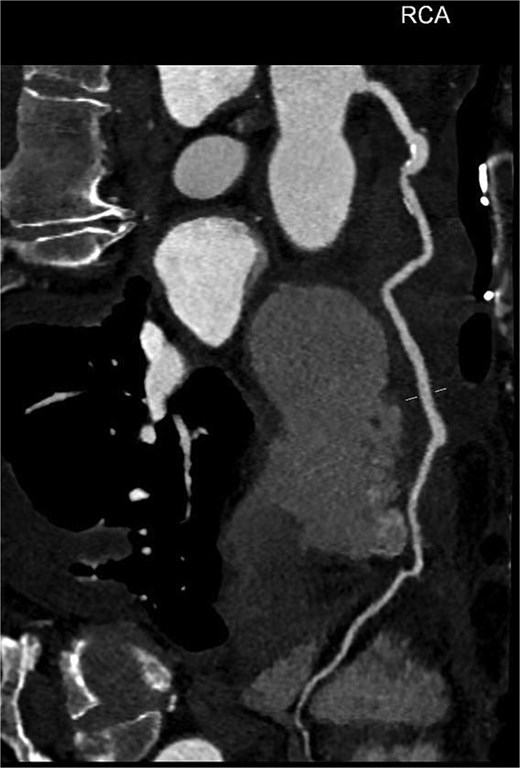

An 82-year-old female presented to the emergency department complaining of progressive severe central chest that was pleuritic in nature, radiating to her right arm. Following a bedside echo, the patient underwent coronary angiography, where a giant right CAA was diagnosed (Fig. 1). Subsequent, contrast computed tomography (CT) scan further characterized the aneurysm, and highlighted significant compression was uncovered compressing both the right atrium and ventricle (Fig. 2). The right coronary aneurysm was measured cross-sectional dimensions of 8.3 × 7.4 cm (Fig. 3) and 10 cm in length (Fig. 4). Following Heart Team discussion, the patient was scheduled for an aneurysmectomy and coronary artery bypass to repair the extensive disease.

Axial plane of a contrast thorax CT scan showing the giant right coronary aneurysm.

Coronal plane of a contrast thorax CT scan showing the giant coronary aneurysm.